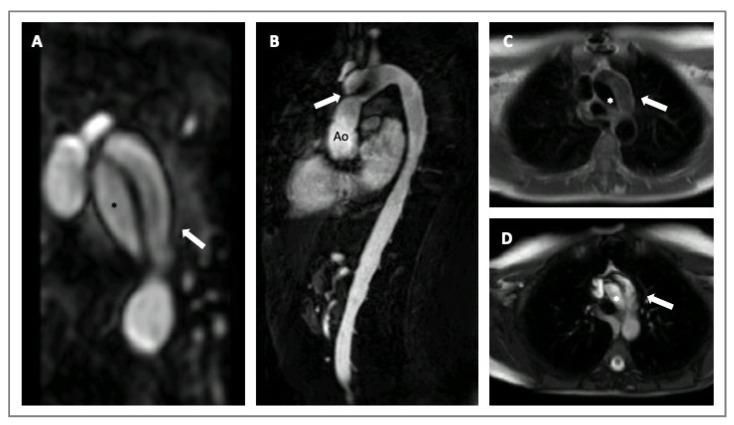

Advances in both imaging techniques and genetics have led to the recognition of a wide variety of aortic anomalies that can be grouped under the term 'hereditary thoracic aortic diseases'. The present review aims to summarize this very heterogeneous population's clinical, genetic, and imaging characteristics and to discuss the implications of the diagnosis for clinical counselling (on sports activity or pregnancy), medical therapies and surgical management.

成像技术和遗传学的进展已使人们认识到多种主动脉异常,这些异常可归类于“遗传性胸主动脉疾病”这一术语之下。本综述旨在总结这一非常异质性群体的临床、遗传和影像学特征,并讨论诊断对临床咨询(关于体育活动或妊娠)、药物治疗和手术管理的意义。